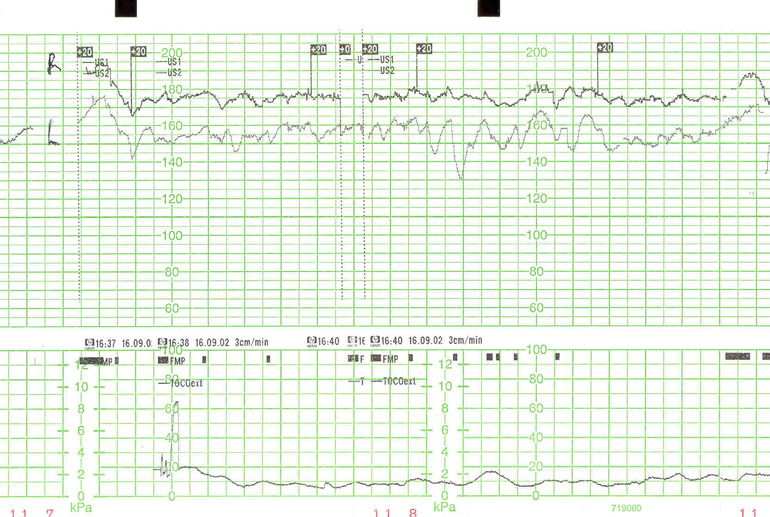

Ну правильно, но аппарат же сам все шевеления улавливает и фиксирует. На бумажной ленте они отмечены черными квадратиками. Он отмечает даже те шевеления которые вы не чувствуете, они отмечены маленькими квадратиками, а сильные толчки которые вы чувствуете, прямоугольниками. А вообще он фиксирует 4 параметра, ваш пульс, СБ малыша, его шевеления и напряжение матки. Поэтому нет смысла нажимать кнопки, все равно аппарат слышит шевеления лучше чем вы.

7df67531782b3b25efa1e3ca0cdfc93f.jpgВ ЖК у нас такой график, данный график верх сердцебиение малыша, низ частота схваток т.к аппарат стоко датчиком, середина фиксация шевелений. Мне честно все равно какой там график, лишь бы с масей все хорошо было.)))

Нет, немного не так должно быть. Вот эти квадратики и есть шевеления, их намного больше чем вы можете почувствовать. Ваш аппарат получается их не ловит, поэтому нужно кнопку нажимать. Но вы правы, главное что бы с малышами все хорошо было. fb233311fe2739527a50ce2eef3d5137.jpg